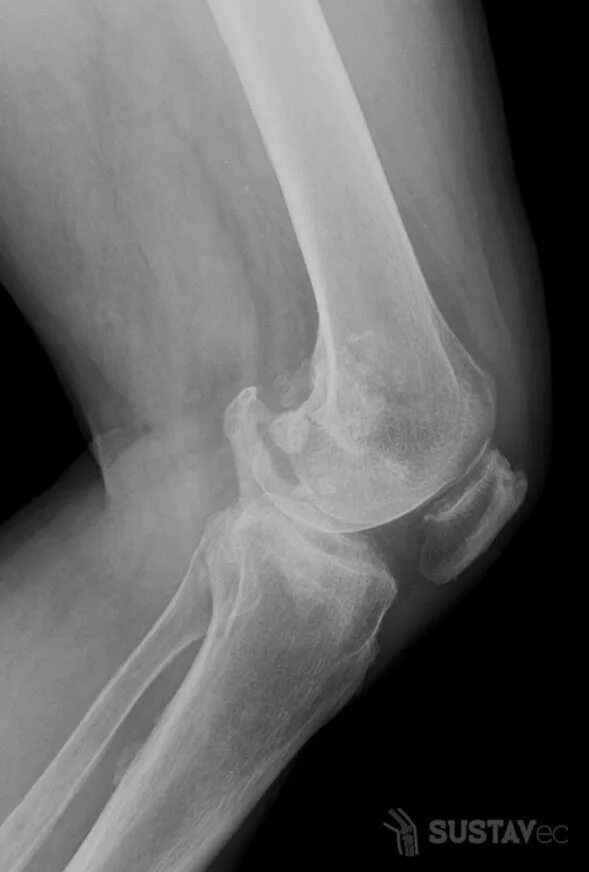

Лигаментоз коленного сустава рентген. тендиноз коленного сустава рентген. пороз коленного сустава рентген. лигаментоз коленного сустава рентгенологическая картина.

Лигаментоз коленного сустава рентген. лигаментоз надколенника рентген. оссифицирующий лигаментоз. лигаментоз тазобедренного сустава рентген.

Деформирующий остеоартроз коленного сустава эндопротез. гонартроз эндопротезирование коленного сустава. деформирующий гонартроз коленного сустава. гонартроз- деформирующий артроз коленного сустава.

Лигаментоз коленного сустава рентген. остеосклероз коленного сустава рентген. лигаментоз тазобедренного сустава рентген. остеосклеротическое поражение костей.

Лигаментоз коленного сустава рентген. оссификация коленного сустава рентген. гетеротопические оссификаты бедренной кости. лигаментоз тазобедренного сустава рентген.